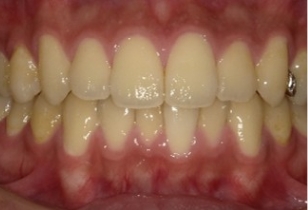

しかし当院の歯並びもよく観察すると、少しは指数が増加、つまり多少は歯並びが悪くなっていることが分かります。実はこれは自然な歯並びの変化と同じものである事がわかりました。つまり歯並びは下の写真が示すように矯正をしてない人でも、変化するのです。その自然な変化をリトル教授のお仲間のシンクレア先生が報告しており、そのデータを追加したのが下の図です(グラフのグレー)。これをみると元々綺麗な歯並びだったものも7年経過するとリトルの指数が35%も増加していることが分かります。

自然な歯の移動